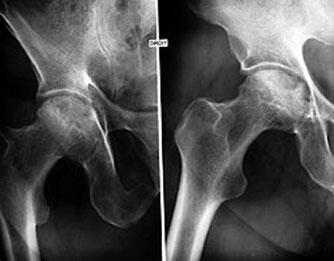

Une des meilleures études en double aveugle a enrôlé 732 patients et les a suivis pendant quatre semaines. Au cours de cette période, 235 d'entre eux ont reçu 1 200 mg de SAMe par jour tandis qu'un même nombre de sujets prenait un placebo ou du naproxène, un médicament classique. La majorité de ces patients avaient des symptômes d'arthrite au genou ou à la hanche depuis environ six ans.

Les résultats ont indiqué que la SAMe soulageait aussi bien la douleur que le naproxène et que les deux traitements étaient significativement plus efficaces que le placebo. Le naproxène agissait plus rapidement, produisant des effets au bout de deux semaines, alors que ceux de la SAMe n'apparaissaient qu'au bout de quatre semaines. À la fin de l'étude, les deux traitements avaient apporté les mêmes niveaux d'effets bénéfiques (Caruso I. et al., 1987).